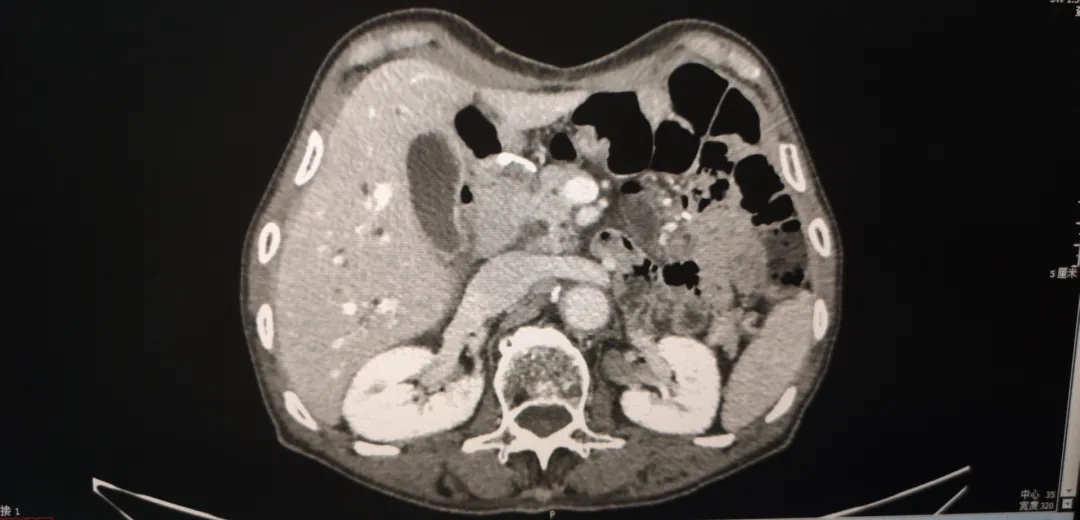

上腹+盆腔增强CT( 2018-8-24 ) :

与2018.5.21腹盆片比较,腹盆腔积液较前增多;胆囊壁稍厚,考虑炎症性改变;腹膜后散在小淋巴结,右侧胸腔少量积液;余无著变。